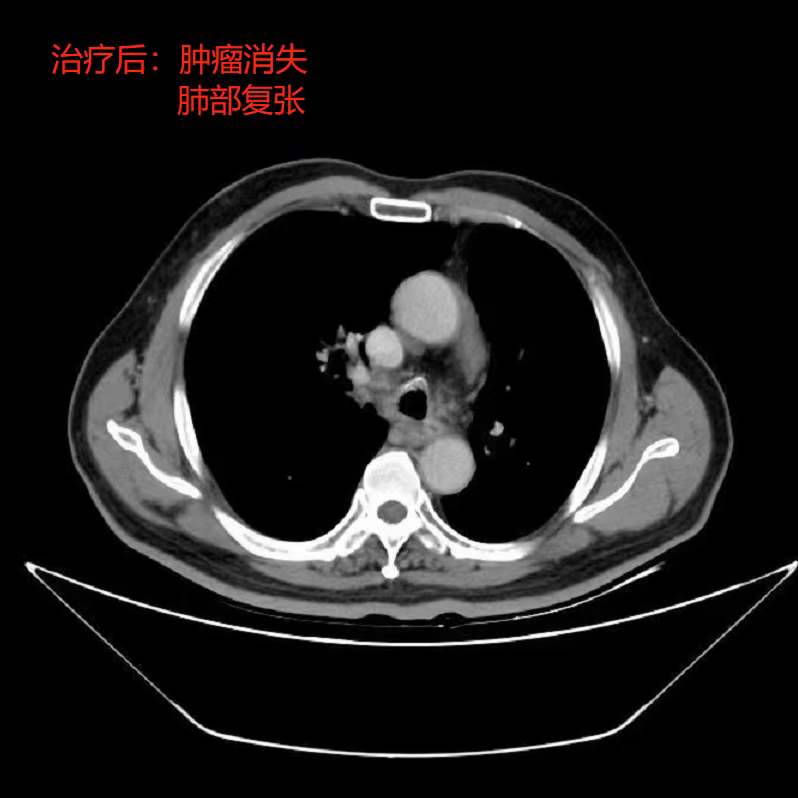

2、支气管神经内分泌癌速锐刀智慧放疗:74岁支气管神经内分泌癌在外院行支纤镜下治疗多次,仅一周时间肿瘤再次生长,并造成阻塞性肺不张。为行速锐刀高精度放疗,慕名而来。顺利完成30次图像引导下精确调强放疗后,出院前复查CT和支纤镜,肿瘤近完全消失,右上肺复张!和家属对治疗的效果十分惊喜。